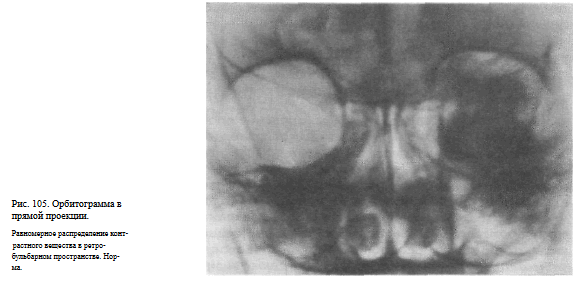

Информативность исследования. Контрастное вещество равномерно распределяется в жировой клетчатке заглазничного пространства и на снимках в норме имеет типичную конфигурацию: на прямом снимке — форму прямоугольника с закругленными краями и округлым дефектом наполнения в центре в месте прохождения зрительного нерва (рис. 105), а на боковом снимке — конусовидную форму с полусферическим вдавлением в области основания, соответственно заднему полюсу глазного яблока.